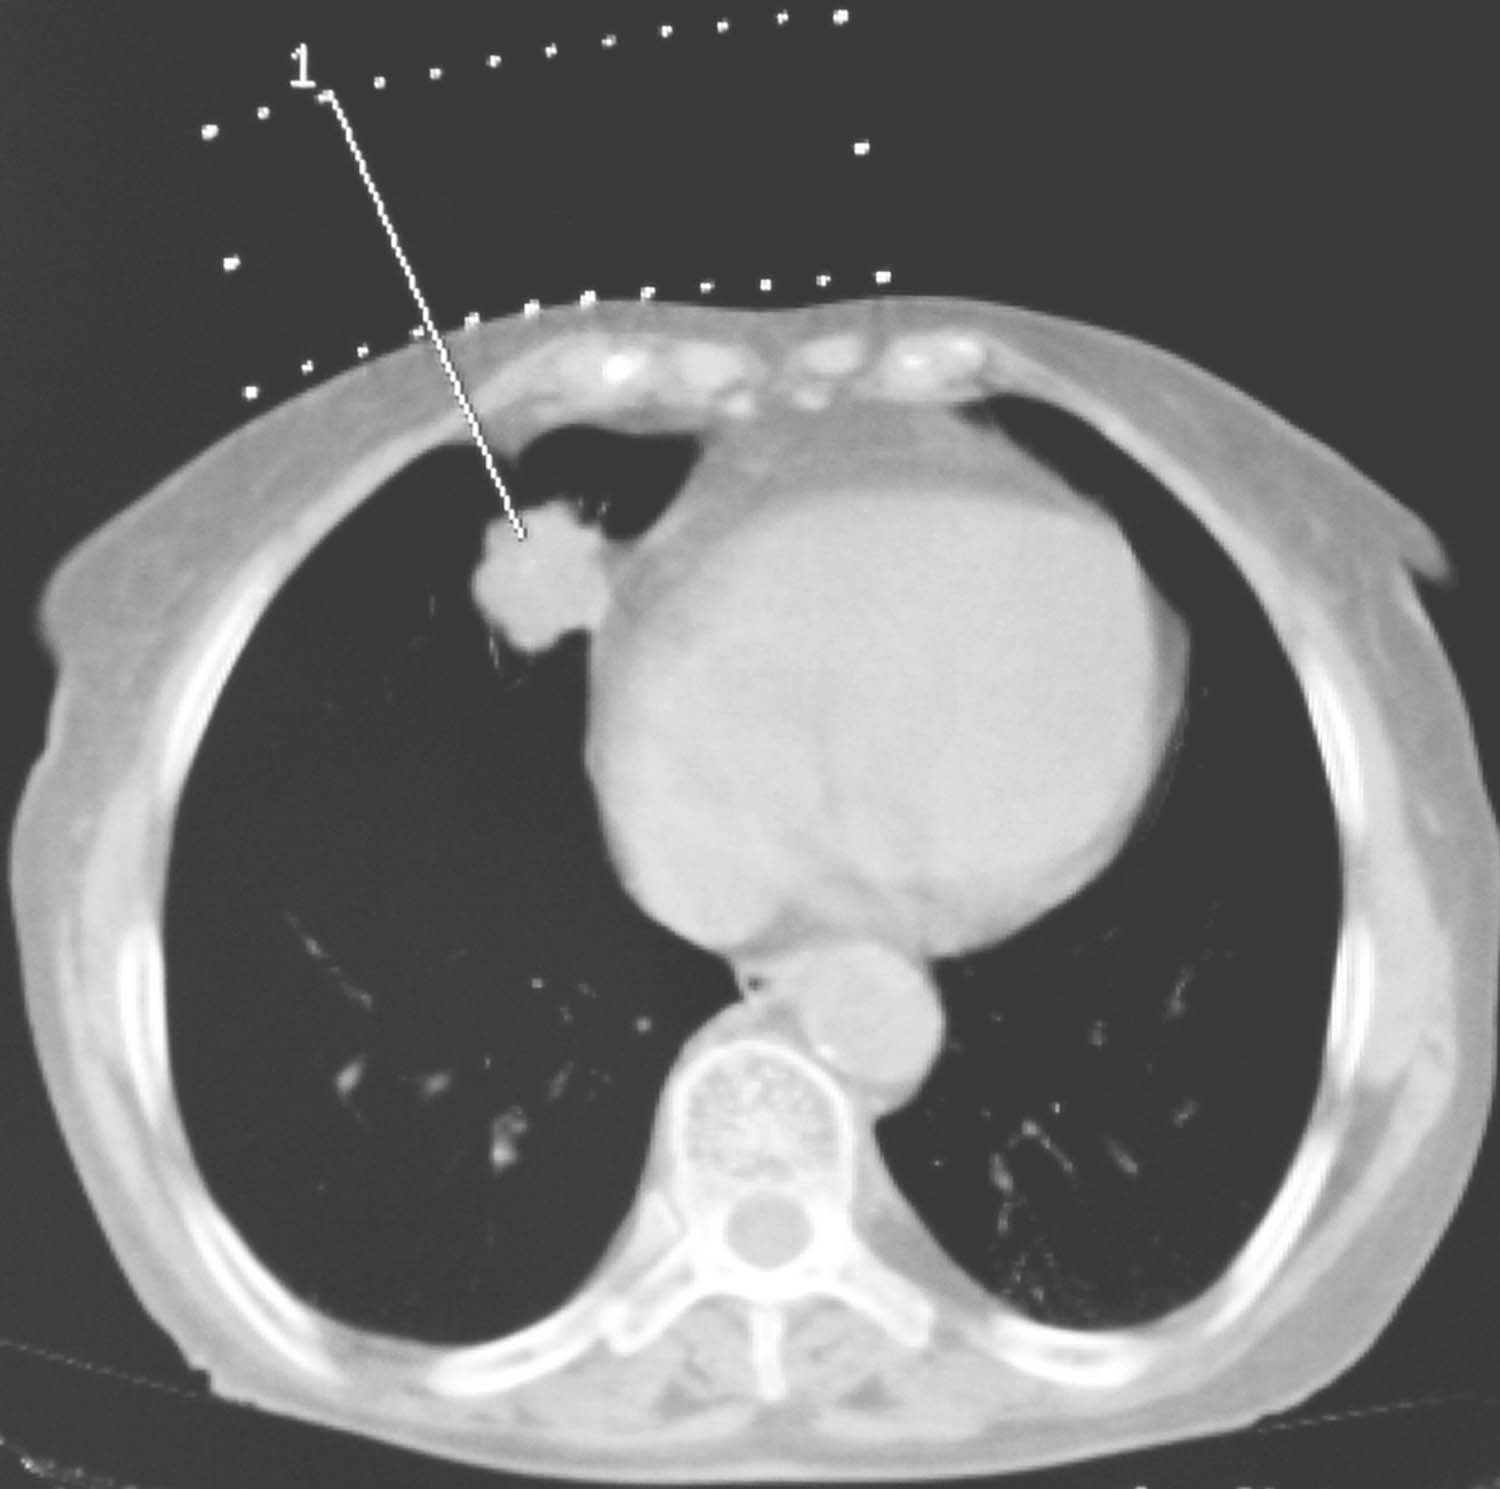

1)勾画靶区和危及器官:靶区勾画尽量遵循外放疗原则,如肺肿瘤一定在肺窗勾画靶区,按不同肿瘤生物学行为外扩一定范围形成CTV。同时准确勾画危及器官,包括可能被手术穿刺损伤的器官和可能出现辐射损伤的危及器官(图4-4-2)。

2)三维重建皮肤、骨骼、靶区及危及器官(图4-4-3):大体观察可能的进针路径,首先看是否肿瘤的各部位均可用共面针道穿刺到位,如果不能完全用共面针道解决,则观察可行的非共面针道进针路径。

图4-4-2 勾画危及器官

图4-4-3 三维重建皮肤、靶区及危及器官